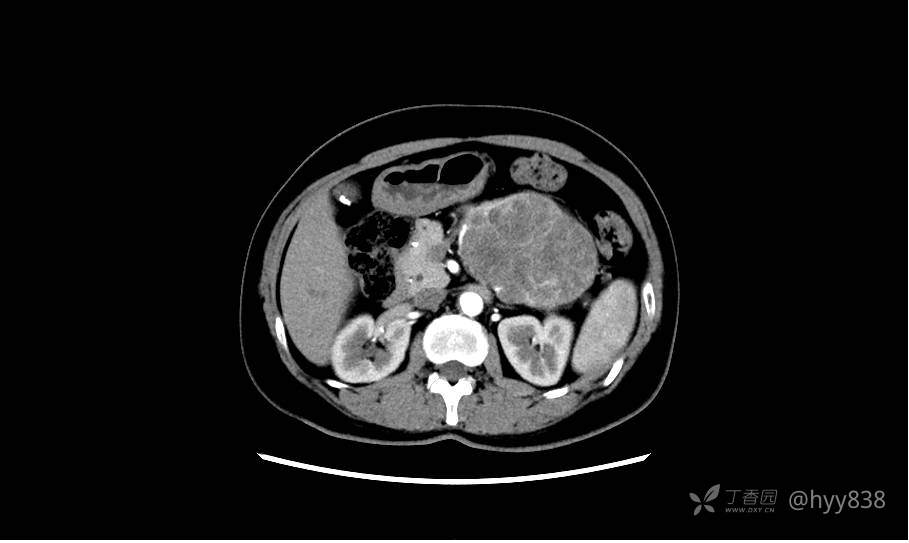

静脉期(机器故障---延迟期了)